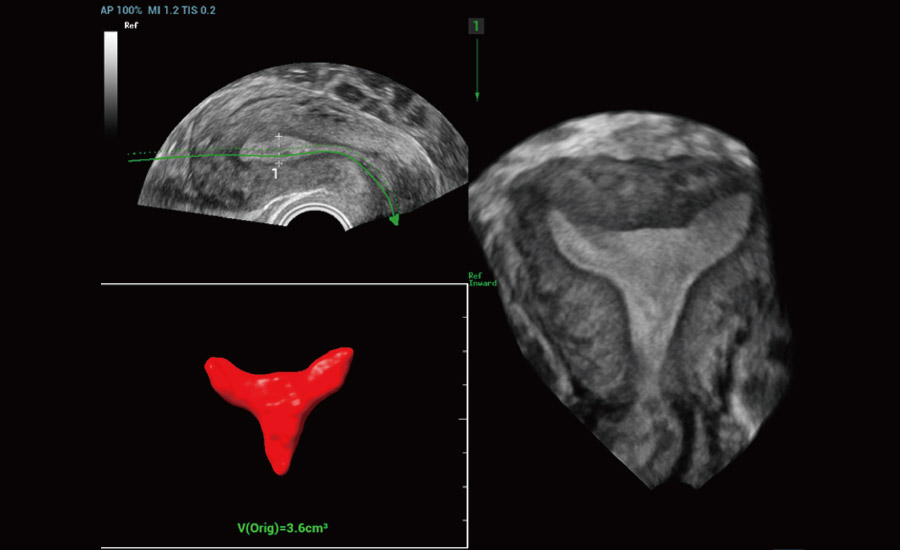

Informa??es abrangentes adaptadas aos cenƔrios

Por meio da combina??o de algoritmos avan?ados e do conhecimento especĆfico da regi?o, a inovadora solu??o Smart Scene permite a identifica??o automĆ”tica das caracterĆsticas do tecido e fornece diagnĆ³stico especĆfico dos Ć³rg?os com informa??es completas. Com base na identifica??o automĆ”tica de cenĆ”rios, a solu??o realiza n?o apenas a varredura 2D inteligente com configura??es e medidas automĆ”ticas, mas tambĆ©m oferece informa??es 3D abrangentes em todas as etapas, desde a otimiza??o de imagens volumĆ©tricas atĆ© a difĆcil obten??o de planos 2D, e a quantifica??o durante todo o procedimento. Ele ajuda a reduzir em grande parte a dependĆŖncia de habilidades clĆnicas, ao mesmo tempo que aumenta a precis?o, a confian?a e a eficiĆŖncia no diagnĆ³stico.

- Cuidando da saĆŗde da mulher com solu??es em ginecologia e uroginecologia

Uroginecologia